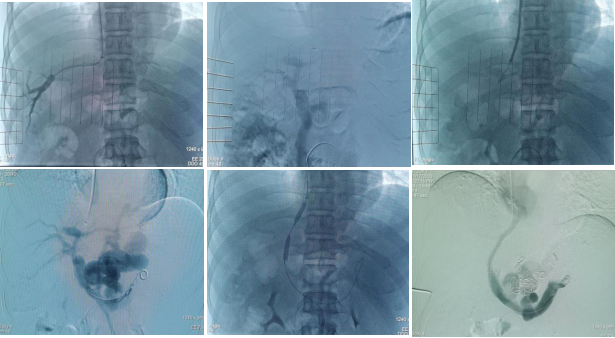

患者,男,43岁,乙型肝炎后肝硬化失代偿期、门脉高压,既往多次上消化道出血,本次因再次急性上消化道出血就诊兰大二院。接诊后,消化内科进一步完善相关检查,行胃镜显示:食管静脉重度曲张并白色血栓头形成、胃底静脉重度曲张。行门静脉CT显示:门脉主干及右支大量血栓形成、食管胃底静脉严重迂曲扩张、脾大、腹水。针对该患者,传统的内科保守治疗和内镜下治疗难以达到预期疗效,TIPS手术是针对此类门脉高压多并发症及门脉血栓的有效微创治疗方案。结合患者既往病史及检查检验结果及多学科讨论后,11月17日,消化内科血管介入团队为该患者实施了TIPS、食管——胃底曲张静脉栓塞手术。术中,测得该患者肝静脉压力梯度(HVPG)及门静脉压力梯度(PPG)均为20mmHg。术后,门脉造影见门脉血流经支架进入下腔静脉,异常食管胃底曲张静脉基本无显影,且门静脉压力梯度(PPG)降至13mmHg。术后复查患者各项临床指标达到正常满意度,TIPS支架血流正常,于11月21日康复出院。